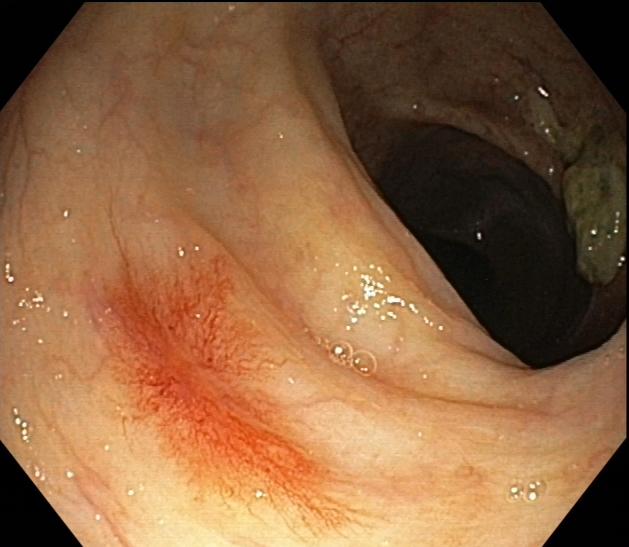

●肠镜检查示:慢性乙状结肠;直肠黏膜炎;结肠蜘蛛痣;外痔。

肠镜显像2

2.皮肤粘膜未见肝掌、蜘蛛痣,结肠镜检可见蜘蛛痣。

肠道蜘蛛痣多见于门脉高压性肠病患者中,直肠、肛管静脉曲张,门脉高压性直肠静脉曲张往往引起下消化道出血;内镜下见多发性樱桃红病变,血管呈蜘蛛样血管扩张以及退行性改变;蜘蛛痣与肝肺综合征、酒精性肝病、肝炎肝硬化、门脉高压性胃肠病、食管胃静脉曲张破裂出血等都有相关性,我院曾收治过因肠道血管病变导致消化道出血的患者,所以临床上仍应高度警惕此类并发症,出现肠道蜘蛛痣时应根据病史、生化检查、影像、内镜等检查综合分析评估,动态观察,谨防出血。